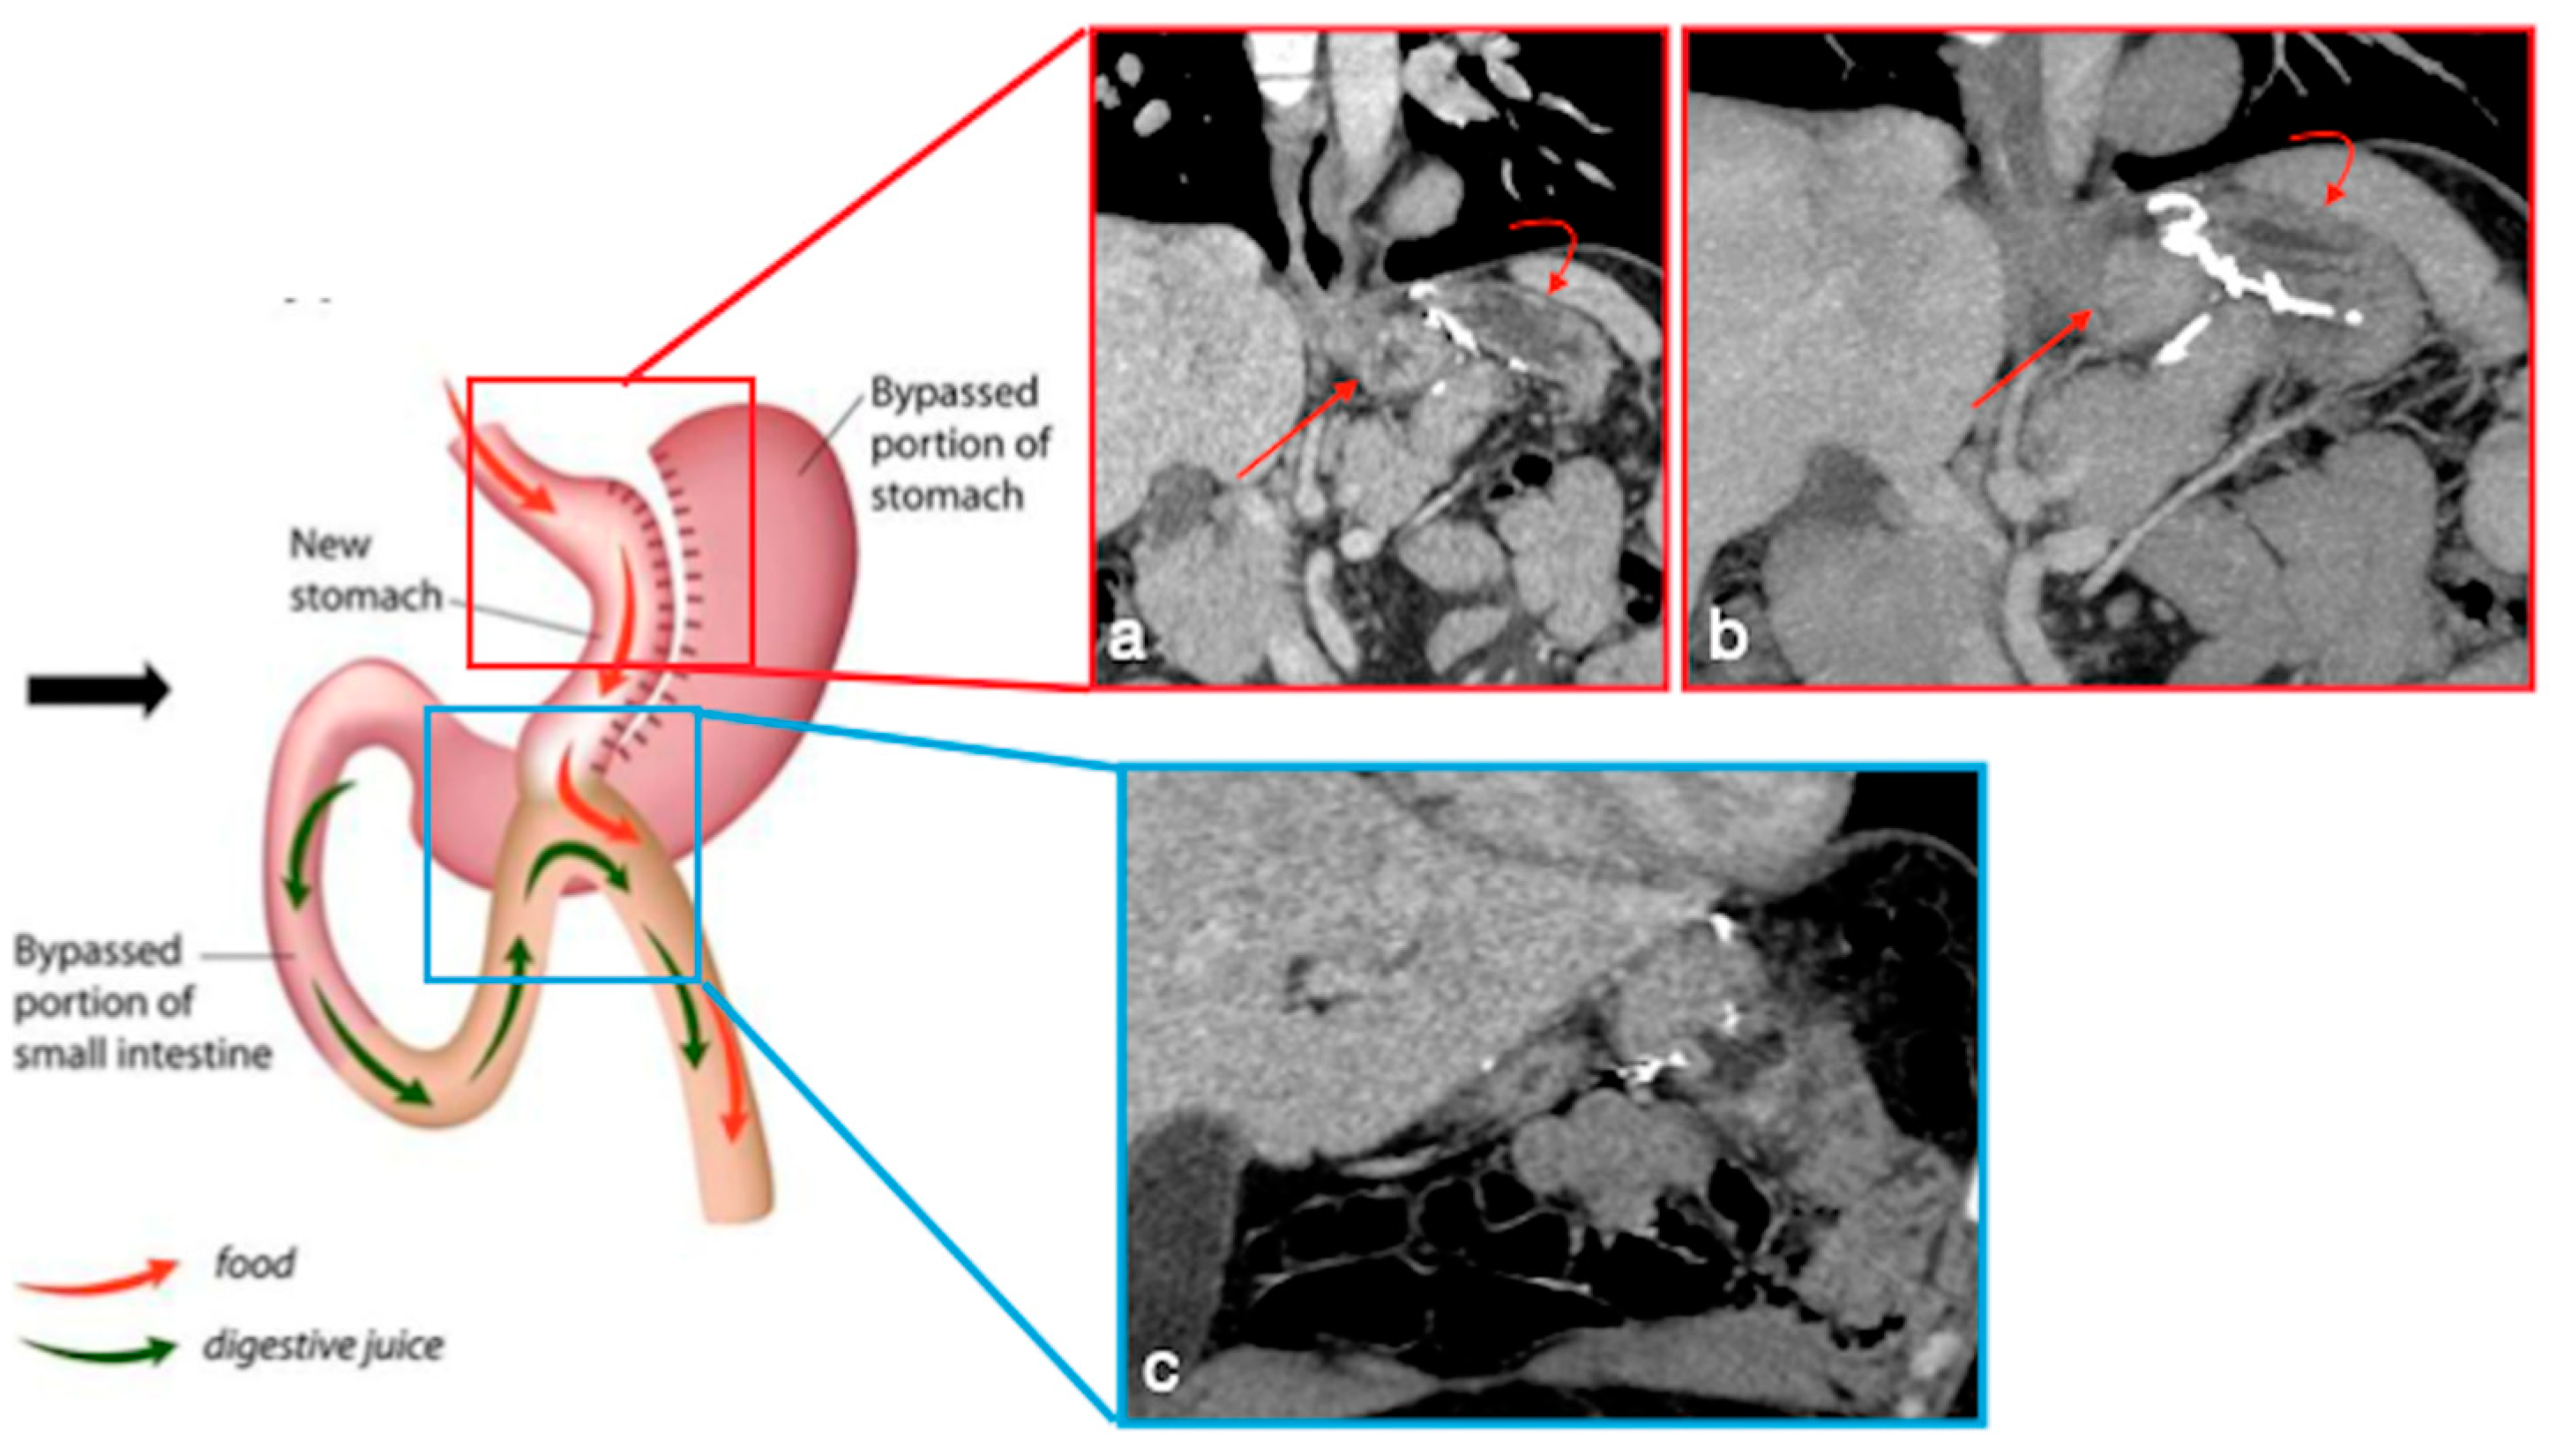

3.3.5. OAGB-MGB

- Marginal ulcers

- Internal hernia

- Anastomotic stenosis

- (a)

- The obstruction involves the alimentary limb, that appears dilated, while both biliopancreatic limb and distal common channel are hypotonic.

- (b)

- The obstruction involves the biliopancreatic limb, which appears dilated, whereas the alimentary limb and distal common channel are decompressed. This closed-loop obstruction could determine perforation of excluded gastric cavity. On UGI, there is a dilated and fluid-filled limb (biliopancreatic) excluded by an oral contrast passage that could determine a mass-effect on the other bowel loops. Upon CT, detection is easy, and it should be suspected not only for the biliopancreatic limb appearance associated to decompression of alimentary and common channel, but also for the recognition of dilatation of excluded gastric room.

- (c)

- The obstruction involves the common channel; any bowel loops upstream appear dilated [4].